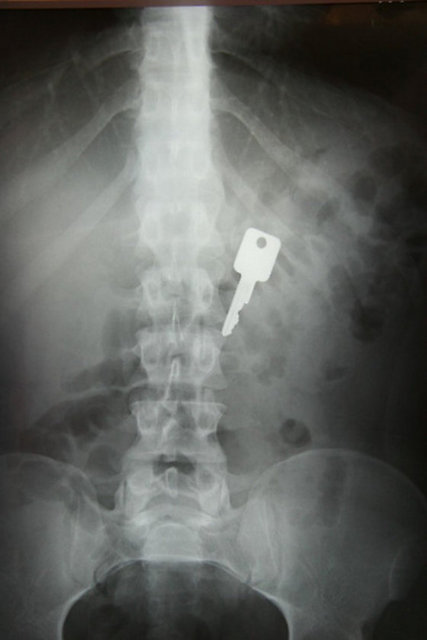

"Özellikle havaalanlarındaki girişlerde iki tür cihazı da görebiliriz. Eşyaların geçirildiği X-Ray cihazında X ışınları kullanılarak görüntüleme yapılır. Çantaların içinde ne olduğu X ışınları ile görüntülenir. Burada uygulanan X ışınlarının eşyalara bir zararı yoktur, birikmez, eşyalarda radyasyon kirliliği yapmaz. Bu cihazların çevresi X ışınlarının insanlara zarar vermemesi için kurşun paravanlarla kaplıdır."